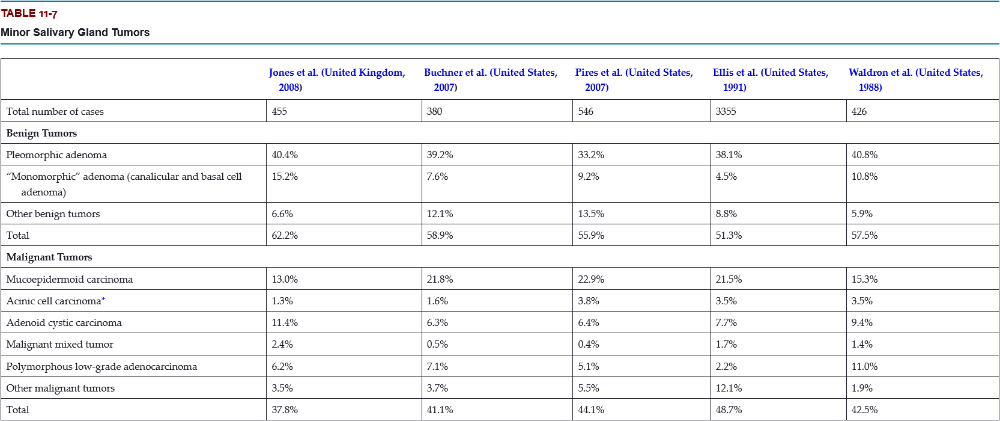

What is the most common malignant tumor of the minor salivary glands?

- mucoepidermoid carcinoma

- acinic cell carcinoma

- adenoid cystic carcinoma

- squamous cell carcinoma

A. mucoepidermoid carcinoma

Mucoepidermoid carcinoma is the most frequent malignancy of minor gland origin, comprising 13% to 23% of all tumors.

What is the most frequent site for a minor salivary gland tumor?

- lip

- buccal mucosa

- palate

- floor of the mouth

- tongue

- retromolar

C. palate

Most of these occur on the posterior lateral hard or soft palate, which have the greatest concentration of glands.

Which is a more common location for minor salivary gland tumors, the upper lip or the lower lip?

Labial tumors are significantly more common in the upper lip, which accounts for 74% to 87% of all lip tumors.

Which are the three most likely sites for a malignant minor salivary gland tumor?

- lip

- floor of the mouth

- tongue

- palate

- buccal mucosa

- retromolar

B, C, and F

Up to 95% of retromolar tumors are malignant because of a predominance of mucoepidermoid carcinomas; most tumors in the floor of the mouth and tongue are also malignant.